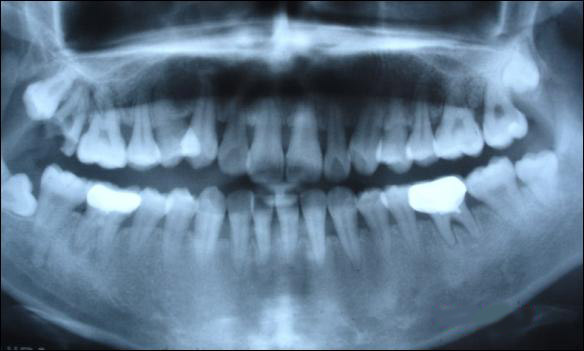

從上圖可以看出,牙槽骨被吸收,牙齦萎縮,牙縫變大